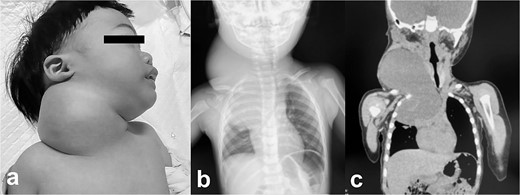

A male infant weighing 2726 g was born at 38 weeks of gestation. Antepartum ultrasonography and magnetic resonance imaging (MRI) revealed a right cervical cyst, suggestive of a lymphangioma. A right cervical cyst was noted at birth and gradually decreased in size thereafter. However, right cervical swelling became evident when he cried (Fig. 1a and b). An MRI obtained at 21 months of age showed a huge cyst in the right cervical mediastinal region. Following diagnosis of a lymphangioma with hemorrhage, he was treated with Eppikajutsuto®, a Japanese traditional Kampo medication, 2 g/d (0.2 g/kg). An MRI revealed tumor enlargement after oral administration of Eppikajutsuto® for 2 months. A complex vascular malformation was noted (Fig. 2) and the dose was increased to 5 g/day (0.5 g/kg). A repeat MRI 2 months after the dose increase showed no reduction in the size of the tumor. After another 4 months, the dose of Eppikajutsuto® was further increased to 7.5 g/d (0.65 g/kg). The tumor in the cervical region had enlarged further with an accompanying risk of airway system compression (Fig. 3a–c). A puncture and suction of the lymphangioma was performed for volume reduction and the content was prepared for bacterial culture. The content was dark red in color, which was consistent with hemorrhage. The white blood cell count (WBC) was 19 190/μl and the C-reactive protein (CRP) concentration was 5.77 mg/dl. He was admitted to the hospital to undergo treatment with intravenous and oral antibiotics. The bacterial culture results were negative. On the 22nd day of hospitalization, the WBC count was 8780/μl and the CRP concentration was 0.39 mg/dl. On the 24th day of hospitalization, a Denver shunt was inserted from the right cervical region to the abdominal cavity to reduce the volume of the cervical cyst to prevent airway obstruction (Fig. 4a–c). A pump chamber with a backflow prevention valve was implanted in the right anterior chest subcutaneous tissue (Fig. 4b). By applying pressure to the chamber, the cyst fluid in the neck was returned to the abdominal cavity. The patient was discharged on the 6th post-operative day. The swelling in the right neck was reduced and the pressure on the trachea was relieved based on the X-ray findings (Fig. 4c and d). On the 5th day after hospital discharge, the patient was febrile and the right neck swelling recurred. A hemogram revealed severe anemia and bleeding within the neck cyst was suspected. He was readmitted to the hospital and on the 2nd day after admission the cervical cyst was punctured, which yielded bloody contents. A transfusion was performed for anemia secondary to hemorrhage in the neck cyst. Sirolimus (1 mg), a mammalian target of rapamycin inhibitor, was added 7 months after starting Eppikajutsuto® due to a concern that administration of a Kampo medication and insertion of the Denver shunt might not be effective. An X-ray showed that the tip of the catheter may have moved within the cyst, which caused the catheter tip to penetrate the cyst and resulted in bleeding within the neck cyst (Fig. 5a). Serial MRI findings showed that the old bleeding site was within the mediastinal region of the lymphangioma. Revision surgery was performed 3 weeks after inserting the Denver shunt. Intraoperative findings showed that the tip of the catheter had penetrated the cyst wall (Fig. 5c). There were cyst walls with a septum on the mediastinal side of the cyst and when incised old bleeding was noted and the walls were opened as much as possible (Fig. 5d). The tip of the catheter was rounded and fixed with threads. The catheter was returned to the cyst and the wound was closed (Fig. 5b). The patient was discharged 9 days after the 2nd surgery. The concentration of sirolimus on the 14th day of administration was 9.9 ng/mL (normal range: 5–15 ng/ml). On the 16th day after the second hospital discharge, the neck had enlarged, the surgical wound was erythematous, and discharge was noted at the site of the pump chamber. Bacterial cultures of the punctured the neck cyst content and the wound discharge grew Staphylococcus aureus. On the 24th day after the 2nd hospital discharge, the blood concentration of sirolimus 1 month after starting oral administration was 19.7 ng/ml. Therefore, the oral administration of sirolimus was temporarily discontinued. At the same time the patient developed a high fever and the 3rd operation was performed to remove the Denver shunt due to a catheter infection. The blood concentration of sirolimus 6 days after discontinuation was 1.4 ng/ml. An MRI on the 6th post-operative day from the 3rd operation revealed two different intensities in the neck and mediastinal regions where the Denver shunt was inserted (Fig. 6a). On the 10th day after the 3rd operation, the patient was discharged from the hospital but laboratory testing showed an elevated WBC count (13 250/μl) and CRP concentration (6.03 mg/dl). Three months after the 3rd hospital discharge, the right neck swelling abruptly decreased in size and the WBC count and the CRP concentration decreased to the normal range. An MRI 2 months after the 3rd operation showed that the mediastinal lesion was smaller with near-complete regression (Fig. 6b). The neck swelling was minimal 6 months after the 3rd operation. An X-ray showed no tumor shadow and no compression of the trachea by the lymphangioma (Fig. 6c) and magnetic resonance angiography (MRA) showed that the lymphangioma had regressed (Fig. 6d). Currently, no right cervical swelling is evident when the patient cries (Fig. 6e and f) and he is doing well with oral administration of Eppikajutsuto® (7.5 g/d [0.65 g/kg]).

Pathologic findings on the first administration. The tumor size in the cervical region was quite large and there may be a risk of airway system compression. (a) physical finding, (b) chest X-ray, (c) plain computed tomography.